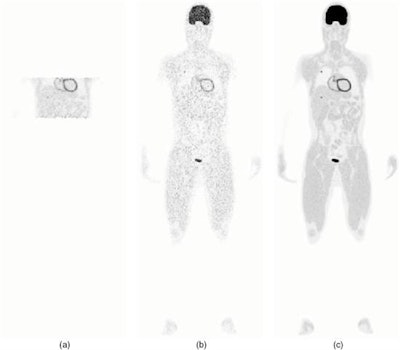

Finally, the team compared EXPLORER with an existing state-of-the-art clinical whole-body scanner. They simulated three protocols: the 36 block-ring EXPLORER with a 197 cm axial FOV; a four block-ring PET scanner with a 21.55 cm axial FOV at a single bed position; and a whole-body scan with the four block-ring system, using 33 bed positions to give a total axial FOV of 197 cm. The scan time was 20 minutes for all cases.

Of the three protocols, EXPLORER produced the best reconstructed image quality. The multibed scan produced a noisy image that did not clearly show the lesion in the liver. The single-bed image exhibited less noise, but was still noisier than the EXPLORER image.

CRC-STD curves showed that with resolution modeling, all three protocols achieved a similar maximum CRC. EXPLORER, however, provided a 6.9-fold reduction in the background standard deviation (27.9%) compared with four block-ring multibed imaging (192%), and a two-fold reduction compared with single-bed imaging (57.3%).